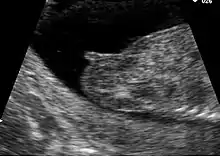

Pregnancy

In pregnancy the vulva and vagina take on a bluish colouring due to venous congestion. This appears between the eighth and twelfth week and continues to darken as the pregnancy continues.[2] Estrogen is produced in large quantities during pregnancy and this causes the external genitals to become enlarged. The vaginal opening and the vagina are also enlarged.[48] After childbirth a vaginal discharge known as lochia is produced and continues for about ten days.[48]